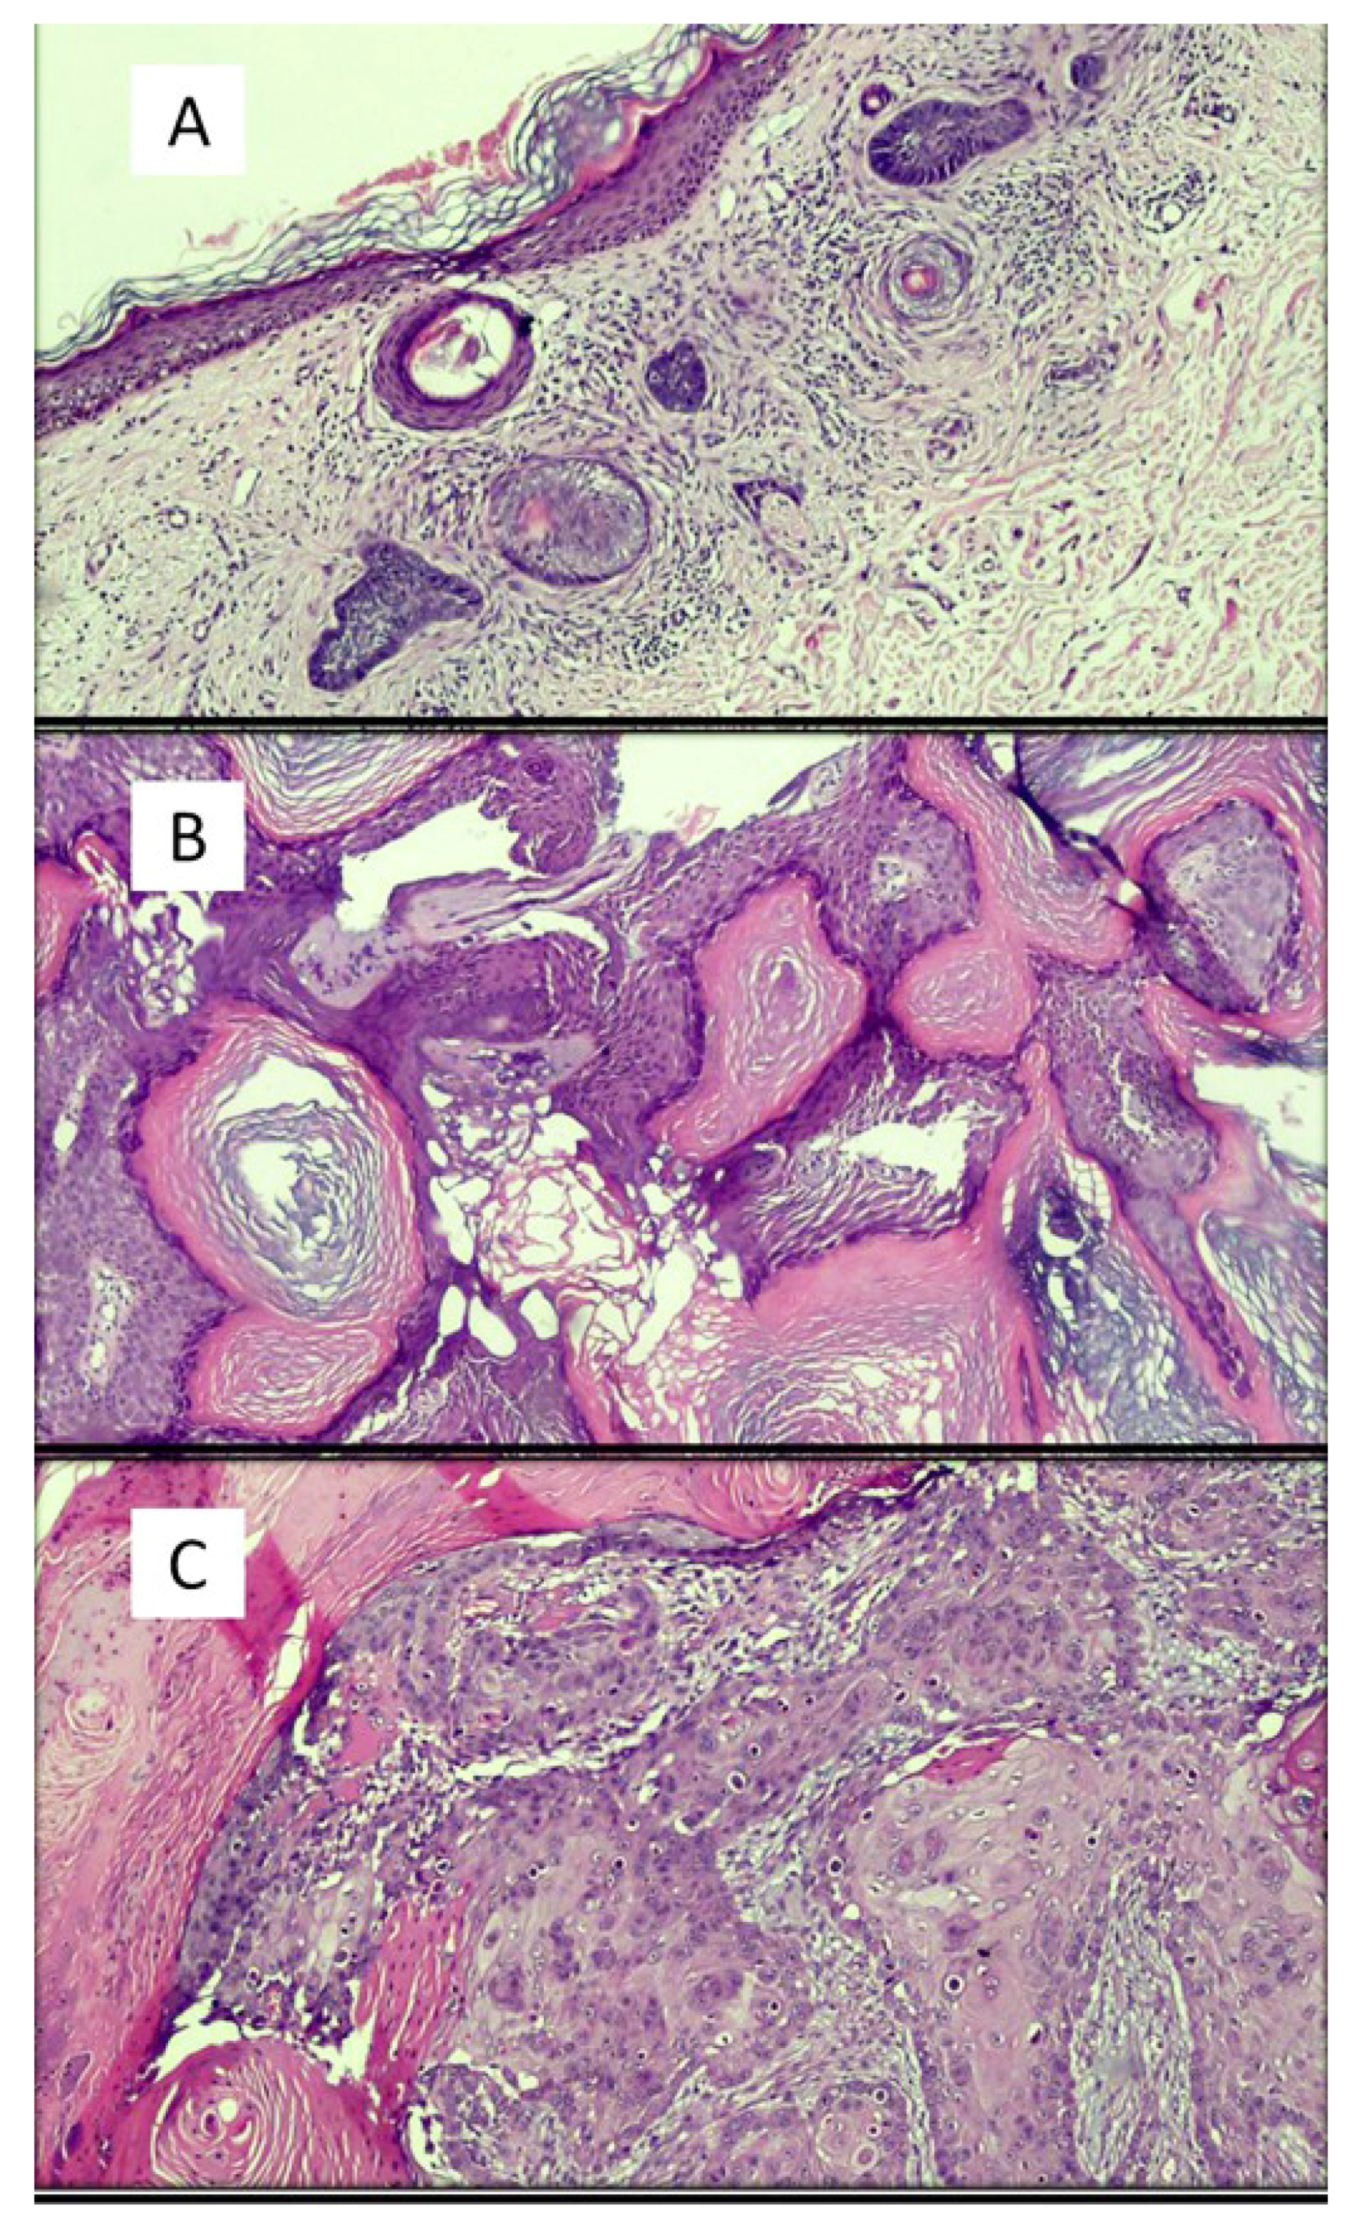

| Olsen et al. [20] | 2018 | Deep learning algorithms | The artificial intelligence system accurately classified 123/124 (99.45%) BCCs (nodular), 113/114 (99.4%) dermal nevi and 123/123 (100%) seborrheic keratoses | Concordance | Difficulty in presenting artifacts, poor coloring |